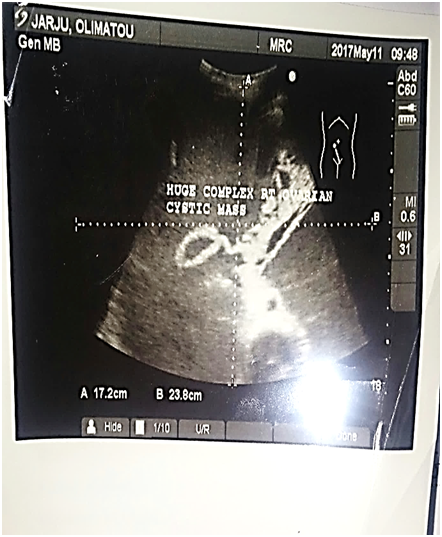

Figure 1 shows the sonographic image of the patient with cystic and solid areas and some characteristics similar to papillary projections (Figure 2) (Figure 3).

Figure 4 cystic mass not ovarian but uterine?.